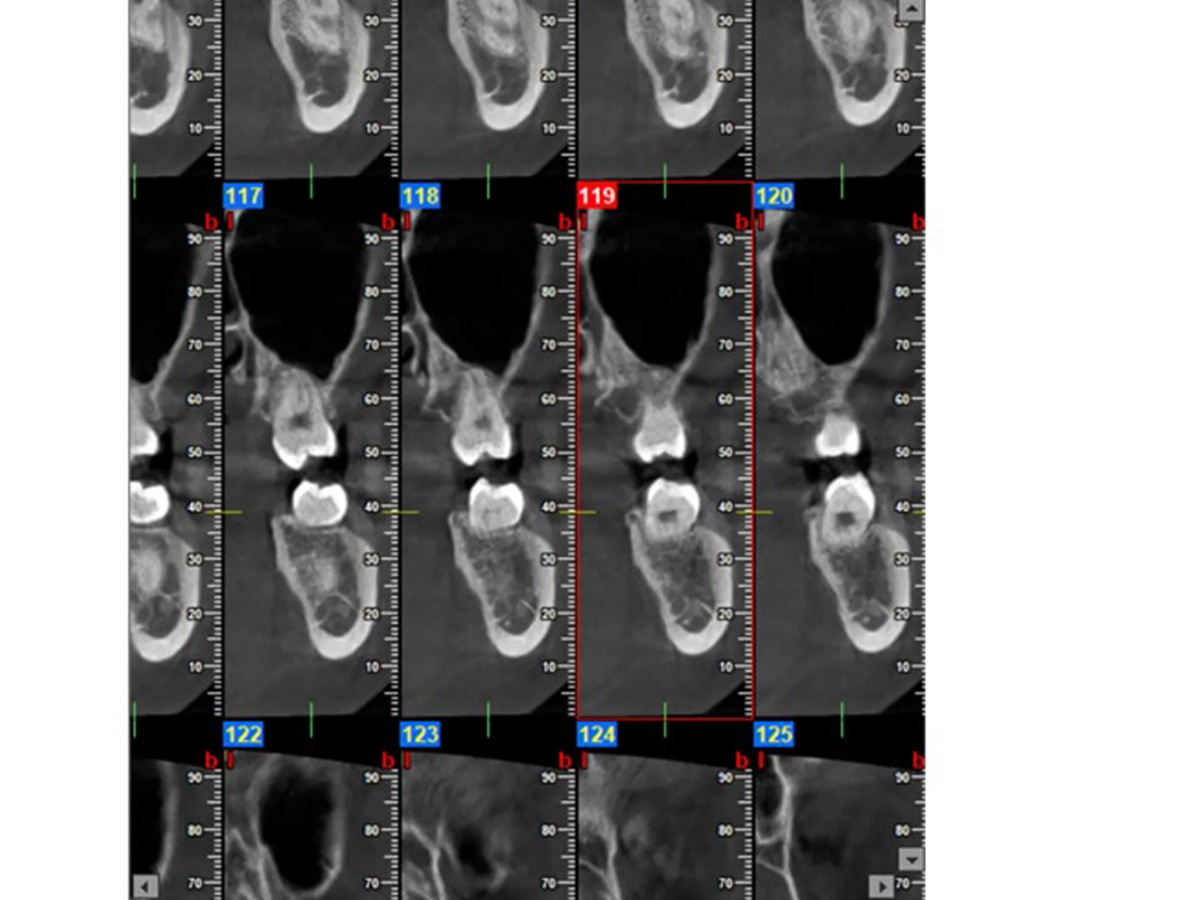

Das größte Problem in der Endodontieist zweifellos der Umgang mit der Wurzelkanal-Anatomie. Diedreidimensionale Struktur des Wurzelkanalsystems stellt eine erhebliche Herausforderung für den Behandler dar. Moderne Feilensysteme ermöglichen in wenigen Schritten eine effiziente Aufbereitung des Wurzelkanalsystems. Zahlreiche Studien aus den letzten Jahrzehnten haben gezeigt, dass die Aktivierung von Spülflüssigkeiten einen entscheidenden Faktor in der endodontischen Therapie darstellt. Erfahren Sie, wie Sie dieDesinfektion in Ihrer Behandlung verbessern können. Biokeramische Zemente sind ein absoluter Gamechanger und ermöglichen eine bakteriendichte Obturation. In praktischen Übungen erhalten Sie wertvolle Tipps für eine bessere Abdichtung des Wurzelkanals. Eine Wurzelkanalbehandlung in einer Sitzung bietet den Vorteil einer schnelleren Schmerzlinderung und verringert die Anzahl der erforderlichen Behandlungstermine, was sowohl für den Patienten als auch für den Zahnarzt eine erhebliche Zeitersparnis darstellt. Zudem minimiert diese Methode das Risiko von Infektionen, da der Wurzelkanal sofort versiegelt wird, was die Erfolgsquote der Behandlung erhöht. Welche wissenschaftlichen Grundlagen dieses Konzept unterstützen und in welchen klinischen Fällen es eingesetzt werden kann, erfahren Sie in diesem Workshop.